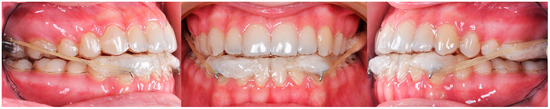

3. The Results of the Treatment